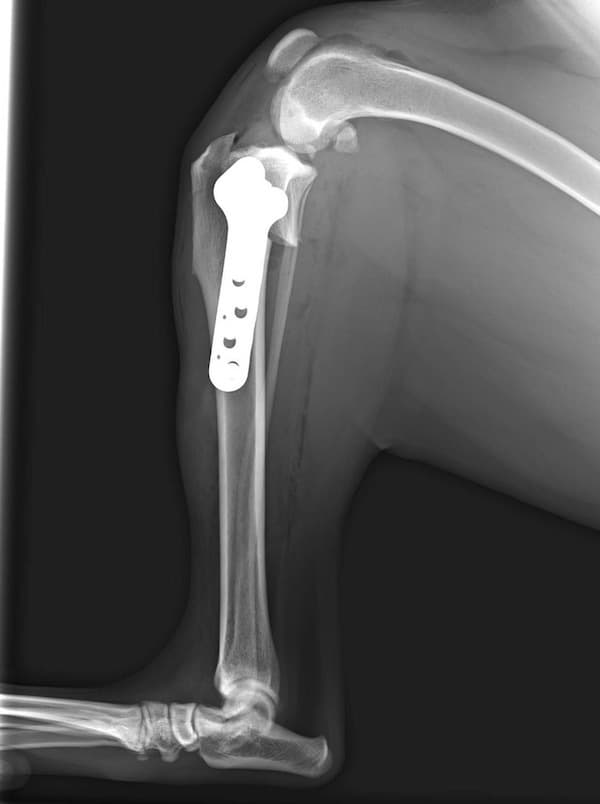

前十字靱帯断裂症例(2025/02/06)

HPの外科の前十字靱帯断裂のページに、犬のTPLO(脛骨高平部水平化骨切り術)手術を行った症例を追加致しました。大腿骨と脛骨を繋ぐ靱帯の一つである前十字靱帯が断裂すると、膝の関節が不安定となり関節炎が進行します。また膝関節内のクッションの役割を果たしている半月板にもダメージが加わり、痛みを生じて正常な歩行が出来なくなります。治療法としては術後の機能回復の早さから、近年ではTPLO法(脛骨の一部を円形に切り、角度を調整し膝関節を安定化させる手術)が多く選択されています。前十字靭帯断裂は中高齢犬によく見られる病気であり、膝蓋骨脱臼に併発することもあります。気になる症状がある場合はお早めにご相談下さい。

獣医師 臼井

症例報告(2024/08/27)

外科の前十字靱帯断裂のページに、犬のTPLO(脛骨高平部水平化骨切り術)手術を行った症例を追加致しました。大腿骨と脛骨を繋ぐ靱帯の一つである前十字靱帯が断裂すると膝の関節が不安定となり関節炎が進行します。また、膝関節においてクッションの役割を果たしている半月板にもダメージが加わり、痛みを生じて正常な歩行が出来なくなります。治療として多くの場合手術が選択されますが、術後の回復の早さなどから近年ではTPLO法(脛骨の一部を切り角度を調整し膝関節を安定化させる手術)が多く選択されています。

獣医師 白石

犬のTPLO(脛骨高平部水平化骨切り術)手術(2024/08/07)

外科の前十字靱帯断裂のページに、犬のTPLO(脛骨高平部水平化骨切り術)手術を行った症例を追加致しました。大腿骨と脛骨を繋ぐ靱帯の一つである前十字靱帯は、断裂すると膝の関節が不安定となり関節炎が進行し、またクッションの役割を果たしている半月板にもダメージが加わることで、痛みを生じて正常な歩行が出来なくなります。治療として多くの場合手術が選択されますが、術後の回復の早さなどから近年ではTPLO法(脛骨の一部を切り角度を調整し膝関節を安定化させる手術)が多く選択されています。